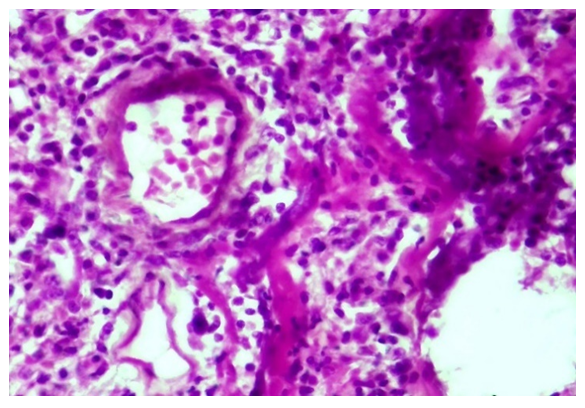

In the first exudative period of COVID-19 infection, when all the bronchioles and alveolar cavities are filled with serous-hemorrhagic exudate, the pulmonary artery's thick branches are sharply expanded, its wall is thinned, a perivascular tumor center appears around it, the blood rheology in its cavity is disturbed, and blood cells, including erythrocytes, are located in a disorderly manner. is determined. It is found that fibrin thrombus has appeared in some of the large branches of the pulmonary artery.It is determined that the composition of the thrombus consists mainly of fibrin with a fibrous and coarse homogenous appearance, in its central part it is thinned and vacuolated foci are formed, and white blood cells and pigments are located in such foci (Fig. 2). One side surface of this thrombus is observed to stick to the blood vessel wall. The wall of the vessel is thinned, some places are hardened, the staining is reduced, strong edema has developed around the vessel. When the small blood vessels of the lungs are carefully studied under the microscope lens, it is determined that fibrin clots appear in their cavity. In the case of COVID-19 infection, as a result of the development of a strong and scattered discirculation process, which continues with diffuse damage to the blood vessels of the lungs, endotheliosis, endotheliitis, coagulopathy, the formation of blood clots, vasculitis, microvasculitis, serous-hemorrhagic-fibrinous exudate accumulates in the alveolar tissue of the lung, and the alveolar tissue becomes deventilated. thickens, the first period of croupous pneumonia is similar to the period of blood transfusion, and red jaundice develops. | Figure 2. A fibrin thrombus has appeared in the large branch of the pulmonary artery, and the presence of thrombus in the capillaries. Stain: H-E. size: 10x10 |